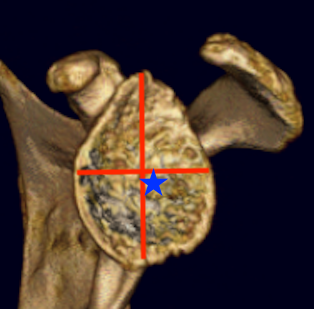

Glenoid center point crucial

Vault is a triangle

- pilot hole critical

- must not penetrate vault with keel or peg drilling

- get vault perforation / blowout

- cannot pressurise cement

Vault blowout / perforation

1. Freehand technique

- identify center of glenoid articular surface

- glenoid center point slightly inferior and anterior to center of the articular surface glenoid

- match inclination of glenoid

- insert guide pin aiming anteriorly